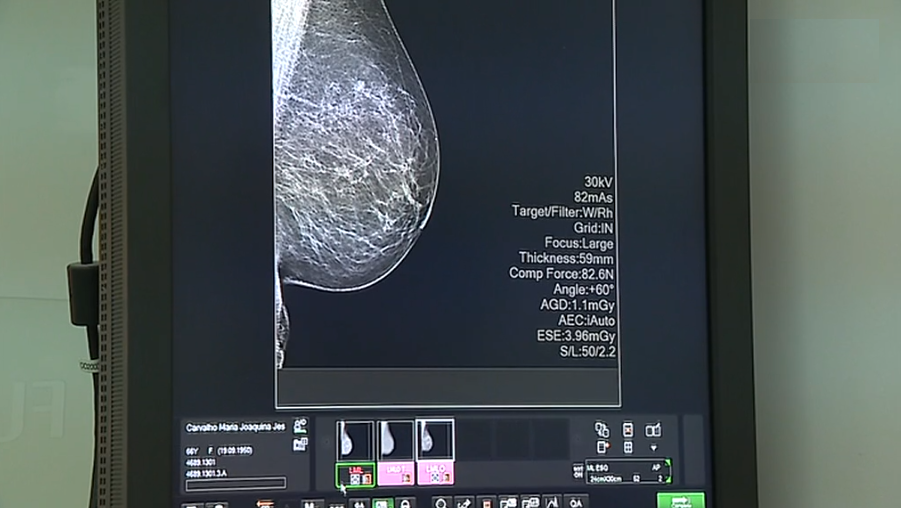

Jornalista Daniel Catalão entrevista em estúdio, Diamantino Gomes, chefe de Serviço de Cirurgia Oncológica do IPO do Porto, sobre a incidência do cancro gástrico em Portugal.

• Temas: Saúde